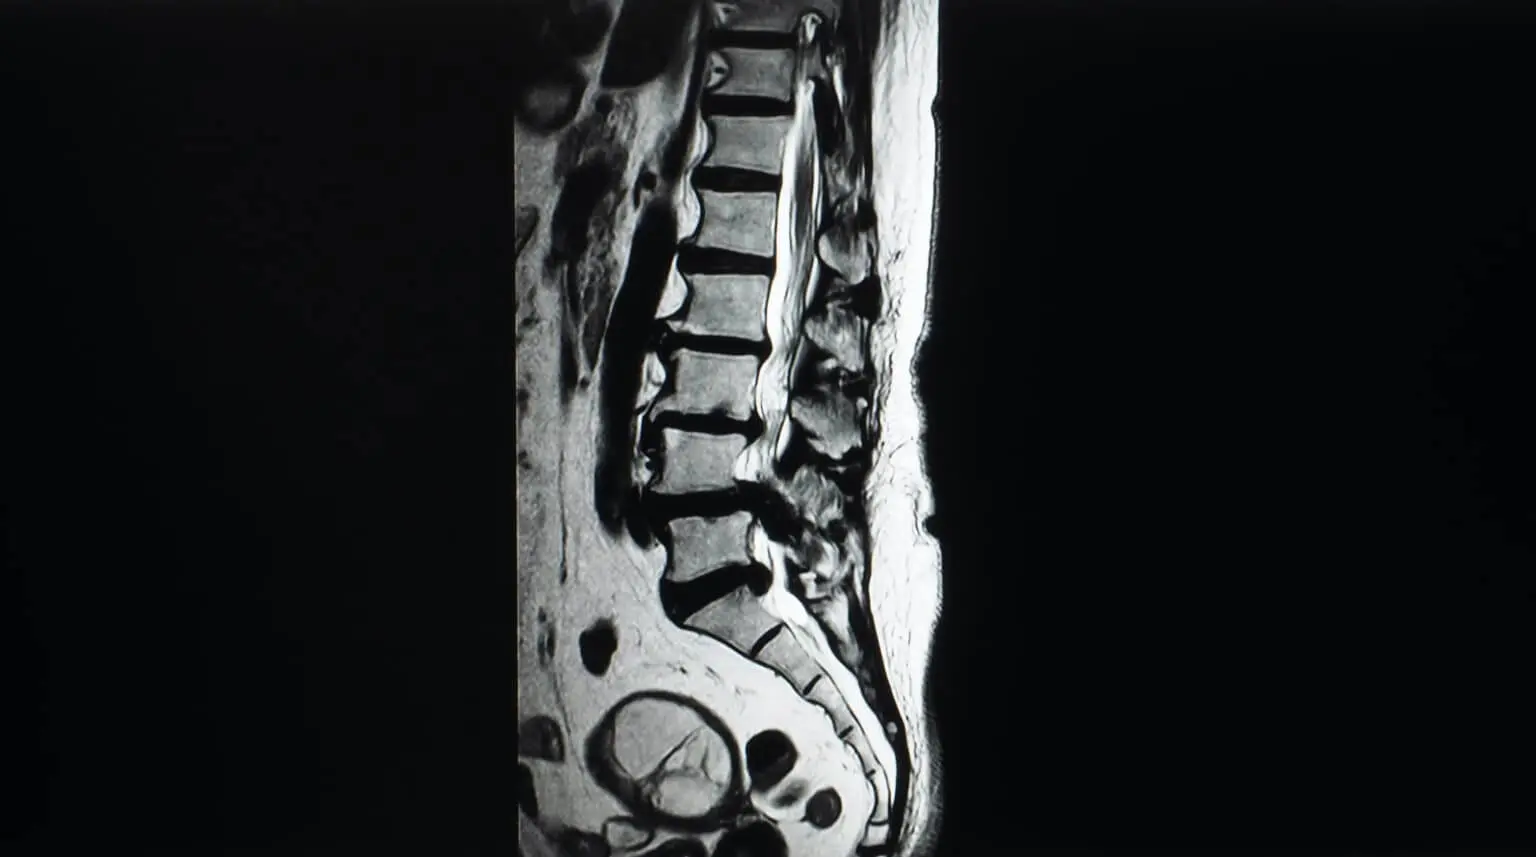

Son yıllarda altın standart olarak görülen tanı yöntemi manyetik rezonans görüntülemedir. Bu tetkik ile omurgalar arası mesafede yer alan disk yapıları, omurgaların birbiriyle eklem yaptıkları bölgeler ve omurgaları bir arada tutan bağ yapıları, omurilik kesesi ve buradan çıkan sinirlerin durumlarını değerlendirmek mümkündür. Manyetik rezonans görüntülemede omurilik kanal çapının belirli bir miktarın altına düşmüş olması hastalığın ilerlediğinin bir işareti olarak kabul edilir. Elektrofizyolojik inceleme dediğimiz halk arasında ise sinir ölçüm testi adıyla anılan elektromiyografi ve somatosensoriyal uyarılmış potansiyel tetkikleriyle omuriliğin iletimi ve omurilikten çıkan hangi sinirin bası altında kaldığı ve ne derecede bu baskıdan etkilendiği değerlendirilebilir. Bu inceleme yöntemi ile omuriliği ilgilendiren diğer hastalıklarla ayırıcı tanı yapmak da mümkündür.